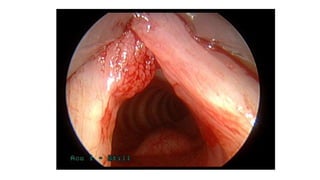

LARYNGOSCOPY-

Laryngoscopy may be performed at any time,

although it is recommended when hoarseness does

not resolve within three months of onset or if a

serious underlying cause is suspected.

Visualizing the larynx and vocal folds is important in

a patient presenting with hoarseness, especially if

symptoms persist.

LARYNGOSCOPY- Laryngoscopy may beperformed at any time, although it is recommended when hoarseness does not resolve within three months of onset or if a serious underlying cause is suspected. Visualizing the larynx and vocal folds is important in a patient presenting with hoarseness, especially if symptoms persist.